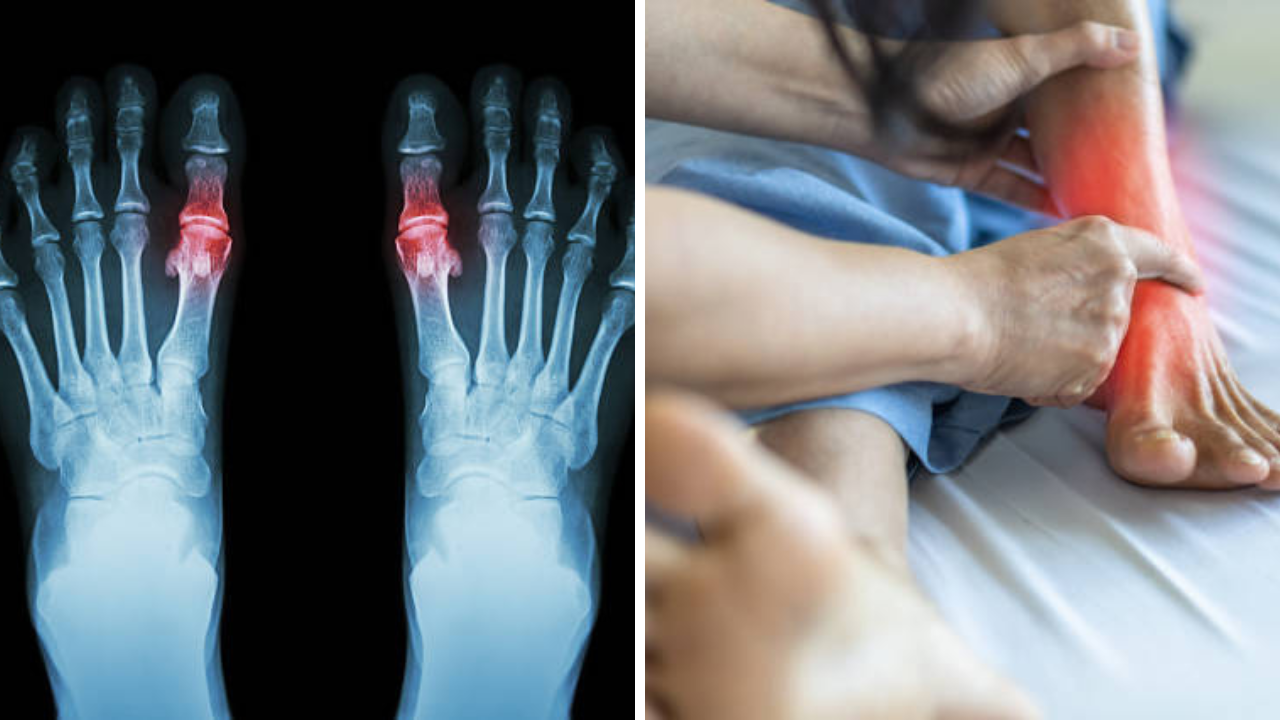

हिवाळ्याच्या आगमनानंतर बहुतेकांना सांधेदुखीचा त्रास होतो. सांधेदुखीपासून सुटका मिळवण्यासाठी लोक सर्वतोपरी प्रयत्न करतात, परंतु काही लोक जाणूनबुजून किंवा नकळत अशा चुका करतात ज्यामुळे समस्या वाढतात. हिवाळ्यात युरिक ऍसिडच्या रुग्णांनी विशेष काळजी घ्यावी. जेव्हा यूरिक ऍसिडचे प्रमाण वाढते तेव्हा ते मूत्रमार्गे उत्सर्जित होऊ शकत नाही, ज्यामुळे समस्या आणखी वाढू शकते. औषधोपचारांसोबतच युरिक ॲसिडच्या रुग्णांनी आपल्या आहाराकडे विशेष लक्ष दिले पाहिजे.

यूरिक ऍसिड चे रुग्णांनी त्यांच्या आहाराकडे विशेष लक्ष दिले पाहिजे. त्यांनी काही पदार्थ, विशेषतः काही भाज्या टाळल्या पाहिजेत. यूरिक ऍसिडच्या रुग्णांनी पालक जास्त प्रमाणात टाळावे, कारण पालकामध्ये प्युरीनचे प्रमाण जास्त असते. पालक खाल्ल्याने युरिक ऍसिडचे प्रमाण वाढू शकते. यूरिक ऍसिडची पातळी वाढल्याने सांधेदुखी वाढू शकते.

हिवाळ्याच्या हंगामात, बहुतेक घरे मोठ्या प्रमाणात मटार आणि बीन्स तयार करतात. तथापि, युरिक ऍसिड ज्यांच्याकडे आहे त्यांनी मटार आणि सोयाबीनचे कमी प्रमाणात सेवन करावे. मटार आणि बीन्समध्ये प्युरिनचे प्रमाण जास्त असते. हे पदार्थ जास्त प्रमाणात खाल्ल्याने सांधेदुखीचा त्रास होऊ शकतो. मटार हिवाळ्यात बाजारात अधिक प्रमाणात आढळतात आणि अनेक मध्यमवर्गीय घरांमध्ये वापरले जातात. पण घरात युरिक ॲसिडचे रुग्ण असतील तर काळजी घ्यावी आणि मटार किंवा कडधान्यांचा वापर कमी करावा. त्यामुळे युरिक ॲसिड वाढून आणखी समस्या निर्माण होण्याची शक्यता असते.

हिवाळ्यात कोणीही भरपूर वांगी खात नसले तरी ज्यांना युरिक ऍसिड आहे त्यांनी ते खाण्याचा विचार करावा. वांगी जास्त खाणे धोकादायक ठरू शकते. किंबहुना, एग्प्लान्ट करीमध्ये प्युरीन्स देखील असतात. वांग्याचे सेवन केल्याने शरीरातील वेदना आणि सूज वाढू शकते. त्यामुळे युरिक ॲसिडच्या रुग्णांनी हिवाळ्यात वांगी खाणे टाळावे.